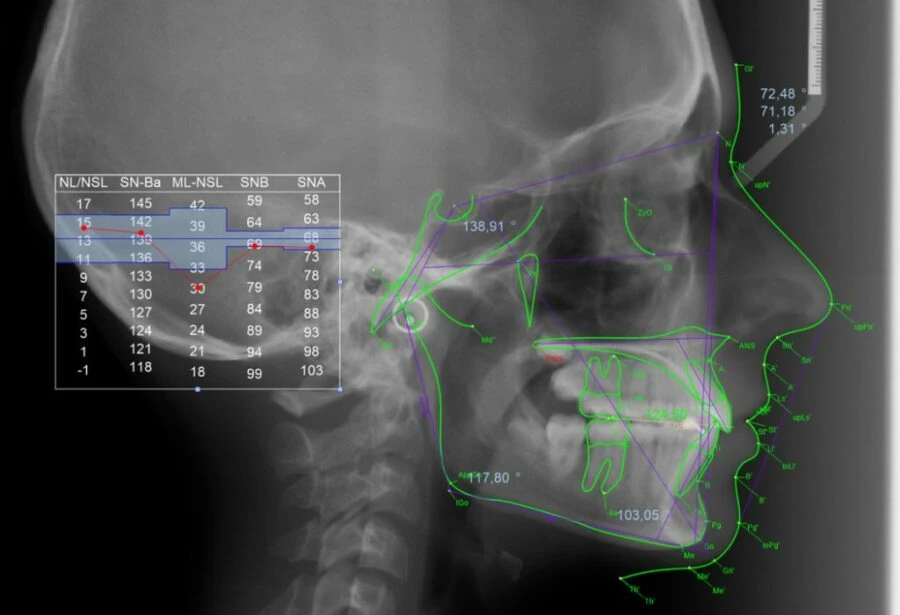

PHÂN TÍCH CEPHALOMETRIC

Phim Cephalometric là một phương pháp tiêu chuẩn để tái tạo lại hình ảnh sọ mặt, rất hữu ích trong việc đo đạt sọ và phức hợp vùng mặt. Vì vậy hình ảnh phim thu được gọi là cephalogram.

Phim cephalometric có thể hữu ích trong việc chẩn đoán và là công cụ đánh giá cho các bác sĩ nha nhi khoa, phục hình, phẫu thuật miệng cũng như các nha sĩ tổng quát. Tuy nhiên, nó chủ yếu phục vụ trong chỉnh nha và vẫn còn là một bí ẩn đối với những bác sĩ ở những lĩnh vực nha khoa khác. Chương này sẽ tình bày những nguyên tắc cơ bản của phim Cephalometric và tóm tắt các phân tích phim thường dùng.

KỸ THUẬT TRACING

Thực hiện tracing cần theo một hệ thống. Đầu tiên nên bắt đầu bằng việc kiểm tra phim cephalogram nói chung và sau đó xác định vị và xác định các điểm mốc chuẩn. Tiếp theo là tìm các cấu trúc giải phẫu theo một trình tự hợp lý, và cuối cùng là xây dựng các điểm mốc và các đường thẳng.

CÁC BƯỚC THỰC HIỆN KỸ THUẬT TRACING